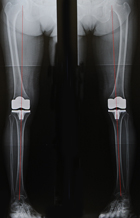

両側同時手術後のX線両脚とも真っ直ぐになっています

患者さんの希望があれば、両側同時手術を行う場合もあります。最初は「片側だけで」と希望された患者さんが、手術を受けるとすぐに「もう片側もお願いします」とおっしゃるケースも多くあります。ただし、無理にお勧めするということはありません。リハビリや入院期間は両側でも片側でもあまり変わりませんが、手術時間は倍になります。手術時間は片側手術で約90分ですから、両側手術では約3時間かかります。また、片側だけだと出血は200cc程度のため輸血はほとんど必要ありませんが、両側の場合は出血量も倍になるため、輸血の可能性を考えて事前に自己血を貯めておく必要も出てきます。確かに、手術が1回で済み、脚の長さを揃えられるため歩行も安定するというメリットは大きいのですが、患者さんの負担面を考慮した上で「まずは片側だけでどうですか?」とアドバイスする場合もあります。なお、症状が3期~4期の間くらいまでの人であれば、より痛い方の膝を手術することで、もう片方の膝の症状が改善することも少なくありません。両側同時手術の適応は患者さんの容態や症状によって変わってきますので、希望される場合には、ご自身の適応や効果、リスクについて事前に医師とよく話し合ってください。